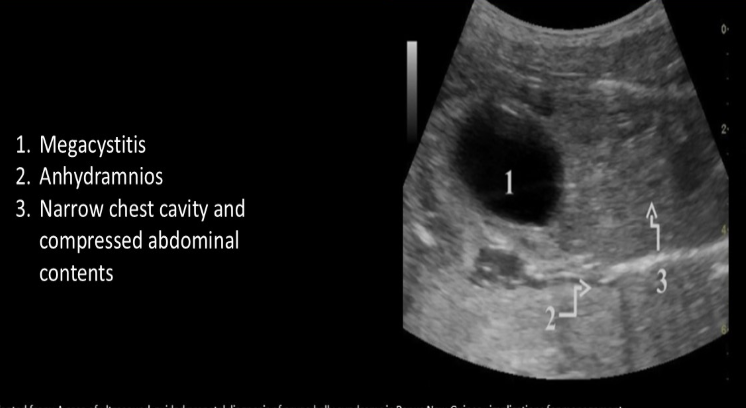

polyhydramnios is an expected finding w/

.

causes a narrowed fetal thoracic cage —> impairs fetal swallowing —> reduces amniotic fluid absorbed from the gastrointestinal tract

a) skeletal dysplasia

b) premature rupture of membranes

c) IUGR

d) potter syndrome